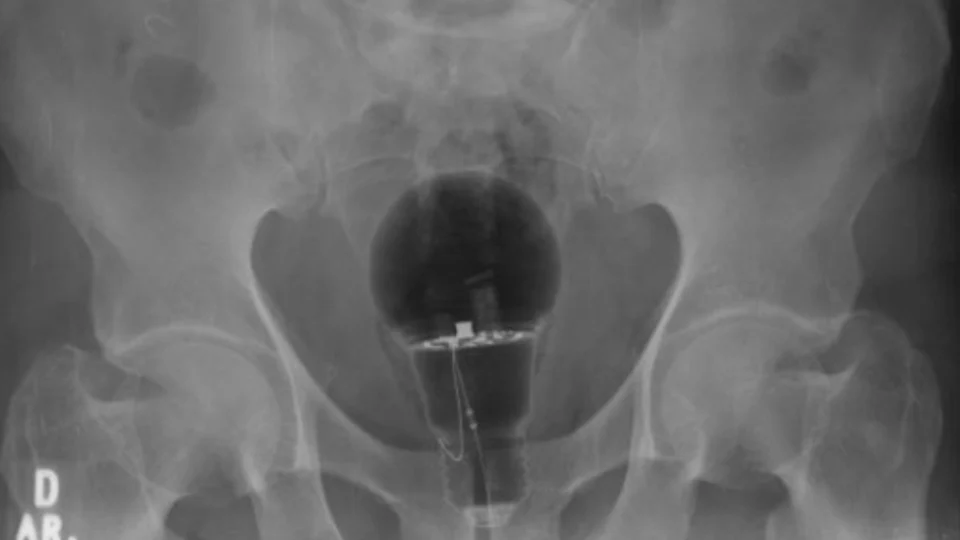

Entretanto, exames de imagem mostraram que uma lâmpada no ânus. Ela teria sido enfiada em seu reto.

“O objeto não era palpável ao toque”, afirmou o gastroenterologista Julian Pylori, que fez o atendimento, em um tweet.